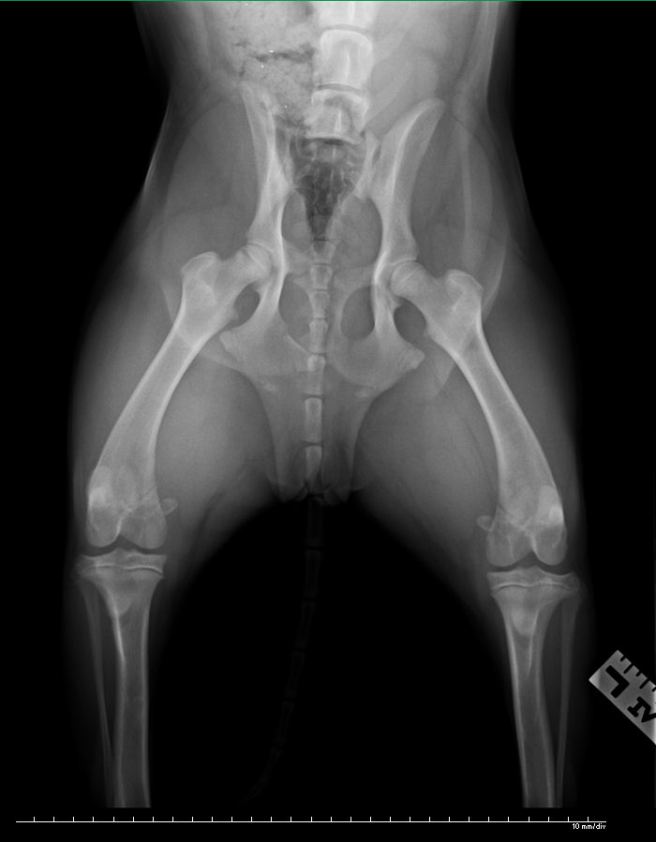

I called the emergency vet clinic on the way and they took her to the back immediately upon arrival. I was asked to fill out paperwork, which I did, scrawling “I have financial limitations.” across the top. After awhile, the vet who had examined her spoke to me about his findings. The injuries did not appear to be grave and he explained that despite the fact that I was being handed an $800 estimate for care that would be ideal, much of it was precautionary in nature. I was given the option to go through the estimate item by item, picking out the services I could afford. He strongly recommended at least one x-ray. I picked out $200 worth of services, including an x-ray. This is that x-ray:

The dog’s pelvis is fractured in 2 places but they will heal on their own, with approximately 6 weeks of cage rest. The vet said, “She got lucky.” I was never so happy to hear 3 words. The vet told me the story of the Good Samaritan from the Bible and thanked me for not leaving the dog in the lobby, which he said happens regularly. He gave me $50 off the bill. They sent us home with pain pills and home care instructions.

Actually, I think Jade is younger the 9 months. Her growth plates are still wide open. Which means she has an even better chance of healing because her bones are so actively growing.

Thanks for letting me know. The vet did point out the growth plates on the x-ray to me. So interesting as I’ve never seen them before. I thought growth plates normally close about 12 months of age but have no idea what the width of hers suggests age-wise. If you have an age guess for Jade based upon what you see in the film, I’d be happy to hear it.